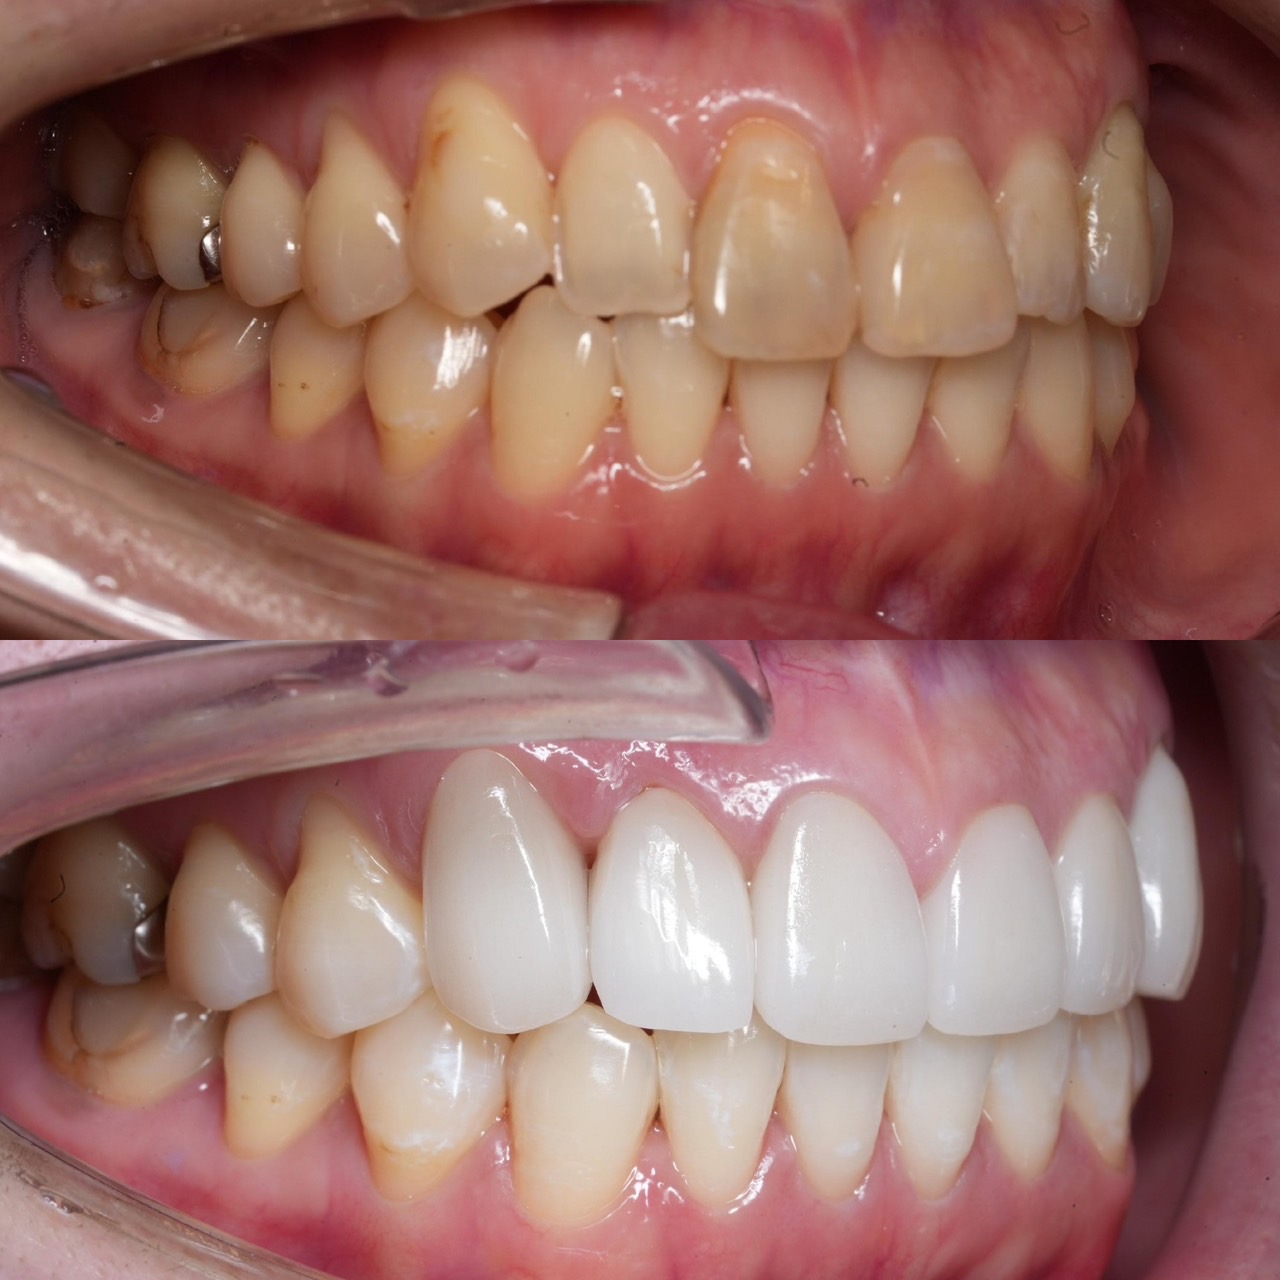

Case029

セラミック矯正の患者様です。

・上下の歯の入れ違い

・正中の歪みと隙間

を主訴にご来院くださいました。

この患者様は若年性歯周炎にかかってしまったため、一生懸命に歯を磨き、口の中は綺麗なのにも関わらず歯茎が下がってしまい、隙間が出来てしまっています。

これは矯正治療で歯の並び方を変えても絶対に無くなりません。

そのため、患者様の主訴を叶えるためにセラミック矯正で治療計画を練りました。

前のクリニックでは「上下一本ずつ抜糸してブリッジで矯正する」という計画だったようですが、

・患者様が非抜歯を希望されていること

・歯を抜かなくても綺麗に並べられそうだったこと

を理由に、当院では上は抜かずにセラミック。下は形態修正だけで対応しました。

この方針変更だけでもお値段も安く、また侵襲(ダメージ)を少なくすることができました。

治療の結果、最低限の侵襲で、見違えるほど綺麗な口元に治療することができ、患者様もとても喜んでくださいました。

【主訴】

・上下で入れ違っている前から2本目の歯のすれ違いを治したい。

・清潔感のある白さで明るい綺麗な口元にしたい

・歯の隙間を無くしたい

【ご要望、ご状況】

・歯を抜かずに治したい

・前医では上下1本ずつ抜歯をして、ブリッジで上3本、下3本の計6本を治すことを提案された。

【今回の治療法】

・右上の犬歯から左の前歯までの計4本をジルコニアセラミックで治療

・色は自分の歯よりやや白いくらいでホワイトニングをしてもしなくても大丈夫なくらいの白さ

・歯は抜かない

・右下の歯は形態修正だけで対応

・歯茎のラインを歯肉整形術で整える